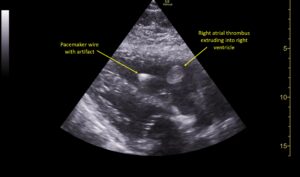

Wolff A, et al. Right atrial thrombosis. Parasternal long US 2, annotated

Wolff A et al. Right atrial thrombosis. Parasternal long US 2 annotated